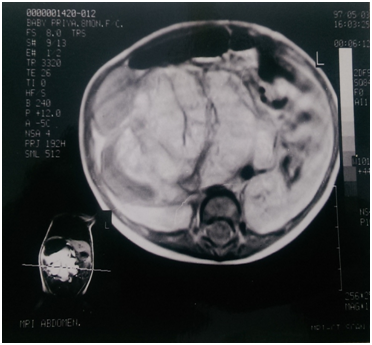

An eight month old male infant weighing 7 kgs was brought with a history of a progressively increasing lump in the right flank of two months duration. There was no associated fever, urinary symptoms or alteration of bowel habits. The child was a full term normal vaginal delivery and developmental milestones were essentially normal. Examination of the abdomen revealed a soft tissue mass approximately 8 x 10 cms in the right hypochondrium causing bulging of the right flank. The mass was ballotable and non-tender and the clinical diagnosis was of a large hydronephrosis. Ultrasound revealed the mass to be a multiseptate, predominantly cystic mass displacing the right kidney posteriorly and inferiorly and was opined to be a cystic neuroblastoma. An IVU confirmed the mass to be superior to the right kidney which was displaced downwards. MRI showed a soft tissue, partially cystic, retroperitoneal mass displacing the liver anteriorly and the kidney downwards (Figure 1) (Figure 2). The right adrenal was not separately identifiable. The mass was filling up the right side of the abdomen and was compressing the IVC in the entire length. Fine needle aspiration cytology from the mass resulted in the aspiration of clear fluid and cytology revealed round cells.

Figure 1 MRI of the abdomen showing the mass having the gross appearance of a brain.

The child was subjected to an exploratory laparotomy and the entire mass, 8 x 7 x 5 cms in size and weighing 486 gms was completely excised. The post operative period was uneventful. Histopathological examination revealed the mass to be a benign retroperitoneal teratoma predominantly containing mature, well differentiated brain tissue in addition to adipose tissue, muscle, gastro-intestinal tissue and stratified squamous epithelium (Figure 3). No immature neural tissue was seen. The interesting thing about this case is that, in retrospect, the mass seen on the MRI looks very similar to a brain (Figure 1). The child has been under follow up for eight years and is doing well.